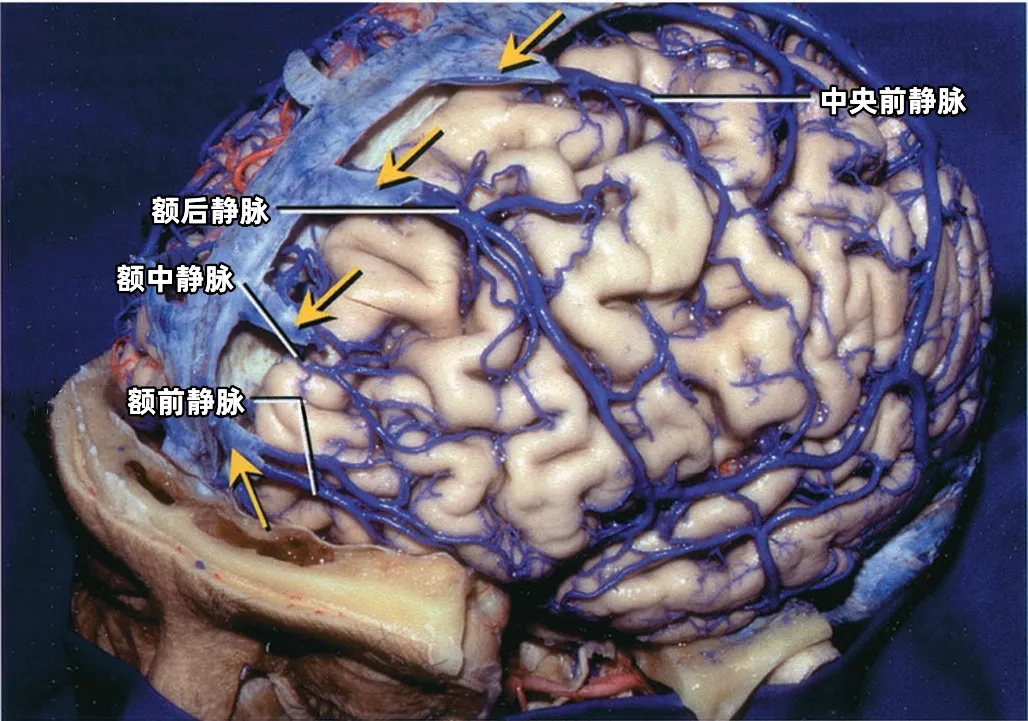

3. 提高手术安全性:尤其关键静脉(如Labbe静脉、中央沟静脉、深部静脉系统)的保护直接影响预后。

学习RHOTON解剖,对脑静脉系统的深入理解,有助于手术的安全操作。